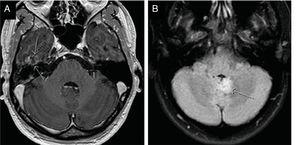

The pathology identified in the ear was schwannomas (Fig. 4), labyrinthitis ossificans, suspicion of retrofenestral otosclerosis, cholesteatoma and semicircular canal dysplasia. Among the extraotic pathology found, in addition to the cavernoma shown in Fig. 4, a low-grade glioma in the cerebellar vermis and a control of a temporobasal brain abscess already practically in resolution stand out (Fig. 5), as well as other alterations of less relevance (ischemic lesions in the brain parenchyma, inflammatory sinusopathy, etc.).